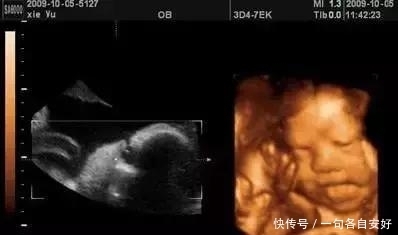

什么是彩超?三维彩超?四维彩超?

彩超并不是字面意义上理解的“彩色的B超”,彩超其实还是黑白的,被称为彩超,是因为会用彩色标注心脏、血流等指标。

三 维彩超、四维彩超的图像则是后期生成的,并不是说观察到的图像就是三维、四维的,而是仍然用普通彩超观察,然后通过仪器中的转换软件将观察到的平面图像转成三维、四维的立体图像。

在诊断的意义上,三维、四维没有任何对诊断更有利的地方,只不过是不懂得B超图像的人也能看出模样而已。它的意义也就在于,您能看见宝宝在肚子里的立体模样了。